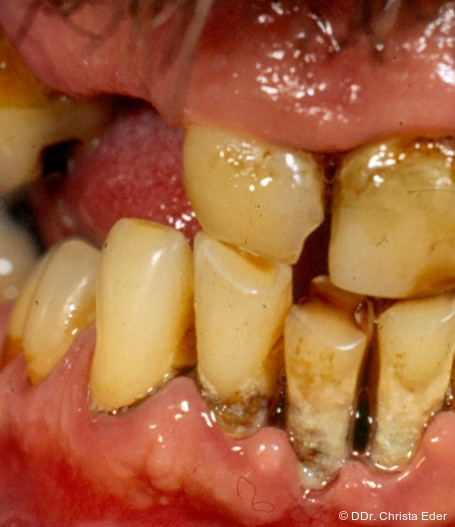

Foto: DDr. Christa Eder

Ein häufiges Problem alter und pflegebedürftiger Personen ist die durch unterschiedliche Faktoren bedingte Fehl- oder Mangelernährung aufgrund einer gestörten, unzureichenden Mastikation.5 Der Mund ist der erste Abschnitt des Verdauungssystems. Zerkleinerung, Einspeichelung des Nahrungsbolus und Schluckvorgang sind Voraussetzungen für eine optimale Verdauung.10 Die im Alter zunehmenden chronisch entzündlichen Erkrankungen des Zahnhalteapparats, periapikale Entzündungen und Karies führen zu einer Reduktion der natürlichen Kaufunktion und letztendlich zum Zahnverlust (Abb. 1). Bei einer Restbezahnung unter 20 ist die Kaueffizienz signifikant beeinträchtigt. Leider verzichten viele ältere Menschen auf eine ausreichende technische Versorgung im Molarenbereich, da der Verlust dieser Zähne nicht als kosmetisches Problem angesehen wird. Zusätzlich verhindert das Fehlen korrespondierender Zähne in Ober- und Unterkiefer einen funktionalen Biss und bedingt dadurch eine Veränderung der Qualität der Ernährung. Weiche ohne Einsatz der Zähne zu zerkleinernde Speisen wie Weißbrot und Kuchen werden bevorzugt. Diese Probleme führen zu einer Atrophie der Kaumuskulatur mit Abnahme der Kieferschließkraft. Die eingeschränkte Speisenauswahl resultiert in einer Malnutrition durch Imbalance in der Aufnahme wichtiger Energieträger. Vor allem der Mangel an Proteinen führt zu Gewichtsverlust, Muskelabbau und krankhaft vermindertem BMI (Body-Mass-Index). Umgekehrt kann aber eine ausschließlich zucker- und fettreiche Kost auch zu Übergewicht bis zu Adipositas führen.1 Eine vorwiegend von Kohlenhydraten und gesättigten Fettsäuren dominierte Ernährung fördert Entstehung und Exazerbation metabolischer Dysfunktionen wie Diabetes mellitus II und Hyperlipidämie. Diese Krankheitsbilder sind eng mit einer Dysbiose des oralen Mikro­bioms und den daraus resultierenden parodontalen und muko­salen Erkrankungen assoziiert (Abb. 2).9, 13